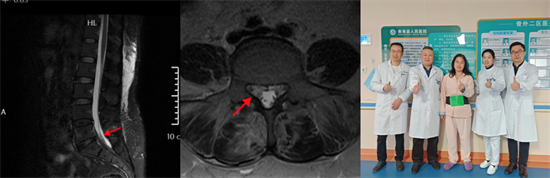

術(shù)前影像資料顯示L5/S1巨大脫出椎間盤(pán)并向近端高度游離

患者陽(yáng)某某,女,50歲,因反復(fù)腰部疼痛7年加重,并右下肢疼痛麻木半月到衡南縣人民醫(yī)院就診。骨科二區(qū)主任陳軾接診了患者,門(mén)診MRI檢查發(fā)現(xiàn)陽(yáng)女士為典型L5/S1巨大椎間盤(pán)脫出并壓迫神經(jīng)根,保守治療無(wú)效,建議手術(shù)治療。苗驚雷教授與縣醫(yī)院骨科二區(qū)專(zhuān)家團(tuán)隊(duì)為陽(yáng)女士量身定制了無(wú)需內(nèi)固定、創(chuàng)傷更小的UBE微創(chuàng)手術(shù)方案。術(shù)中通過(guò)兩個(gè)7mm的切口,精準(zhǔn)摘除脫出髓核,徹底解除神經(jīng)壓迫。術(shù)后次日,陽(yáng)女士下肢癥狀顯著緩解,已可自主下床活動(dòng)。